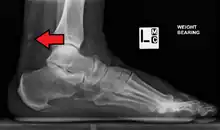

Magnetic resonance imaging may be useful to guide muscle biopsy and to investigate involvement of internal organs;[21] X-ray may be used to investigate joint involvement and calcifications.[22]